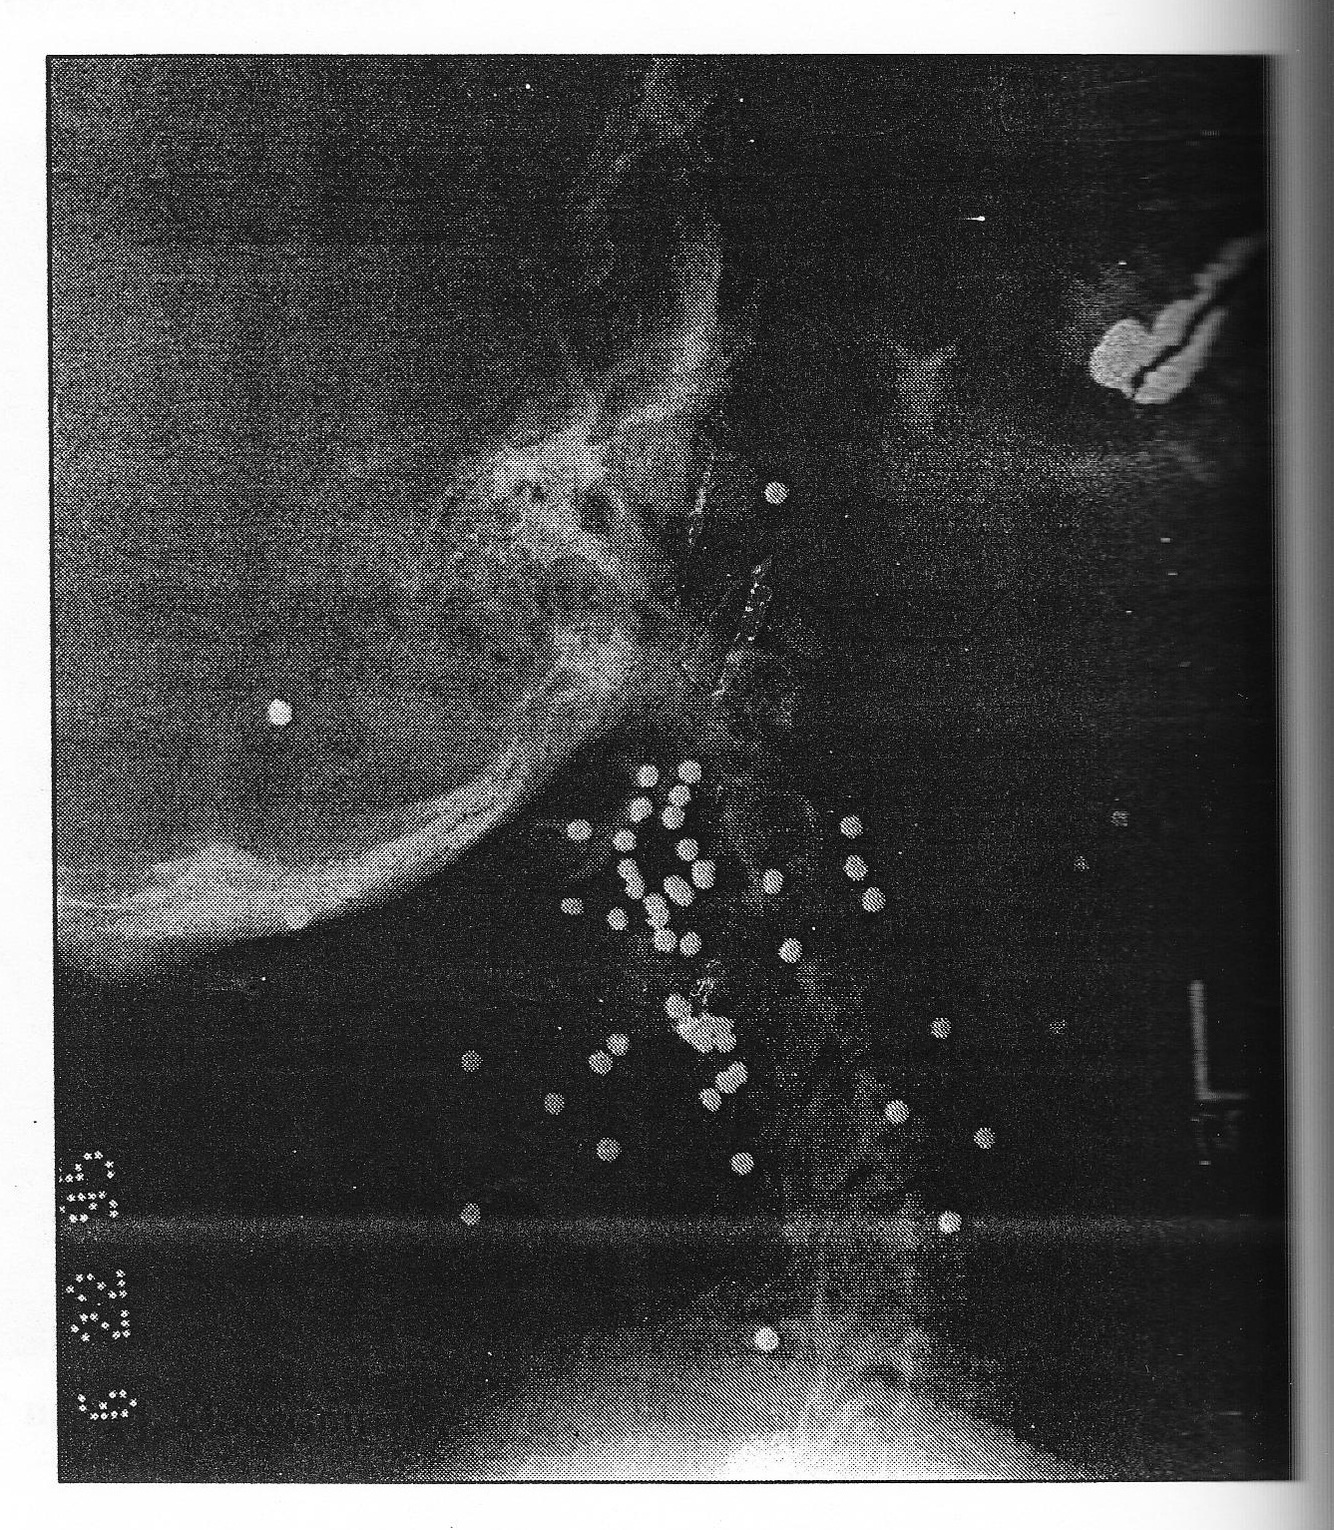

A. Myxopapillary ependymoma of filum terminale

C. Tethered cord with lipoma